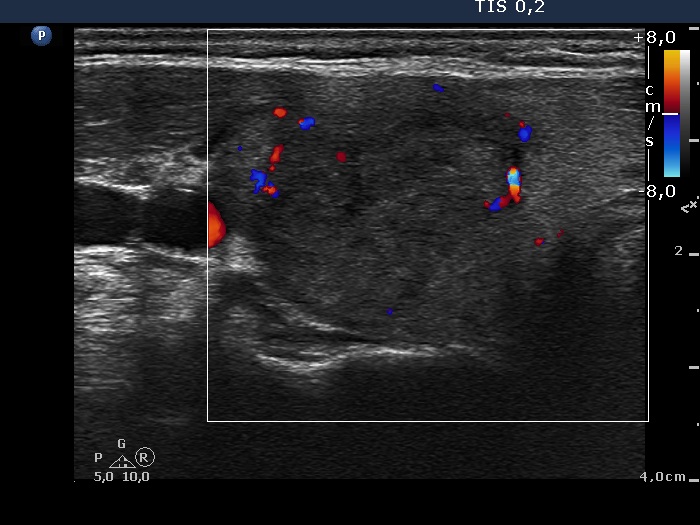

Subacute granulomatous de Quervain's thyroiditis - Case 6. (ultrasonographic picture 3)

Right lobe, horizontal scan. The vascularization is decreased.